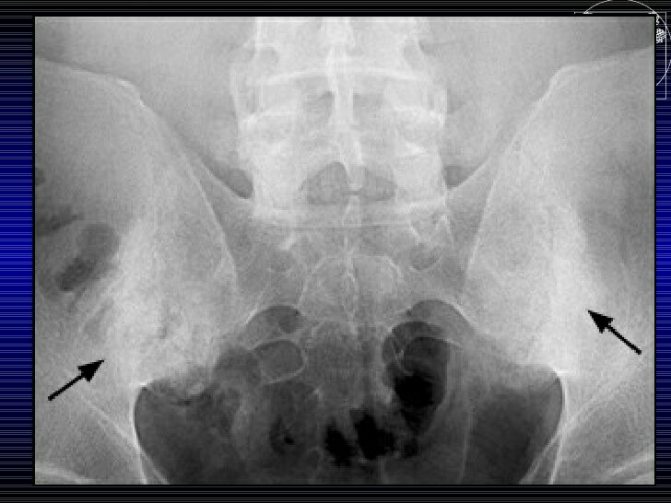

- Рентген можно делать крохе после 1 года. Конечно, при необходимости врачи могут назначить подобное исследование и раньше, но до 7 месяцев на снимке различить состояние суставов будет сложно, так как они еще недостаточно окостенели.

Диагностировать наличие ДТС может специалист, проведя визуальный осмотр ребенка, анализируя рентгеновский снимок и результат УЗ исследования. Поскольку начальные стадии развития патологии визуально определить затруднительно, при малейшем подозрении на наличие проблемы рекомендуется посетить ортопеда.

Для его подтверждения назначаются инструментальные исследования, обычно ультрасонография (УЗИ ТБС). Используется в диагностике и рентгенография, но только у детей старшего возраста. Дело в том, что до 3 месяцев в тазобедренном суставе еще много хрящевых тканей, которые не просматриваются на рентгенографических изображениях.